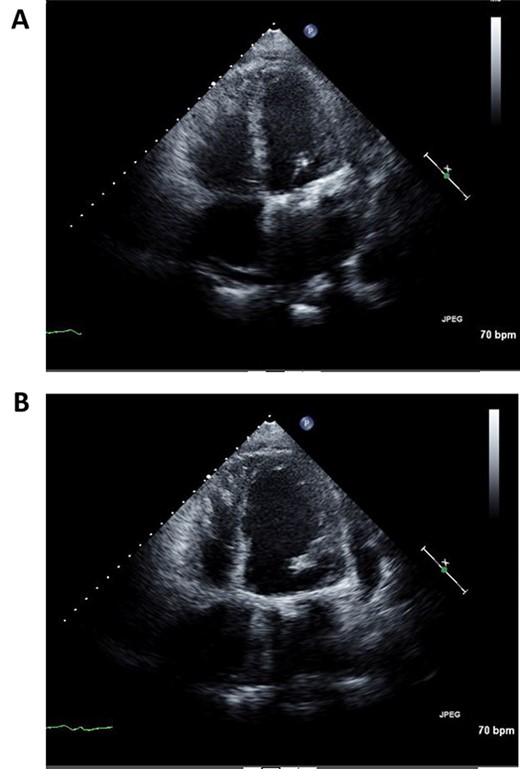

A 50-year-old male who had undergone MV repair 14 years ago due to traumatic mitral valve regurgitation was presented to our department due to heart failure with New York Heart Association (NYHA) III classification. Chest X-ray showed moderate cardiomegaly, and electrocardiogram showed atrial fibrillation with controlled heart rate (Fig. 1A and B). Transthoracic echocardiogram showed moderate MR with severely impaired bi-ventricular function; left ventricular ejection fraction of 20%, (Fig. 2A and B). Coronary angiography showed no significant stenosis. Although indication for mitral valve surgery was marginal [2], surgical intervention was decided to prevent further deterioration of bi-ventricular function.

Preoperative echocardiography of left ventricle in systolic (A) and diastolic (B) phases.